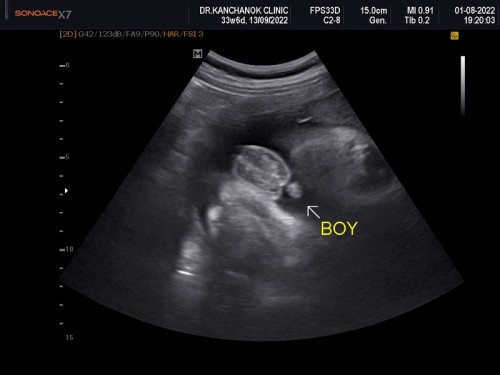

คุณหมอซาวด์ว่าเป็นเพศหญิงตอนห้าเดือน แต่อิแม่ไปซาวด์ที่คลินิกตอนแปดเดือนหำน้องไผล่เลยจ้า อิพ่อนี้อยากได้ลูกสาวมากตั้งชื่อเเล้วเป็นที่เรียบร้อย แต่มาตอนนี้จากลูกสาวมาเป็นลูกชายเลย ตกใจเลยจ้าซาวด์เห็นหำน้อยๆ อิแม่ก็ชื้อของมีแต่ชมพูไว้เยอะเลย ใส่หวานๆไปเลยนะลูก😊 33w6d หนัก 2,400 บ้านไหนน้องน้ำหนักเยอะแบบนี้ไหมจ้าป้าหมอบอกให้หยุดบำรุงเลย กลัวน้องคลอดเองไม่ได้ น้องตัวใหญ่😅